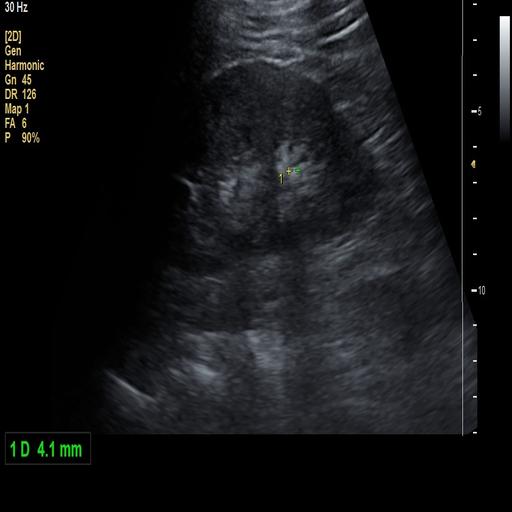

数据样例

结石肾脏样例